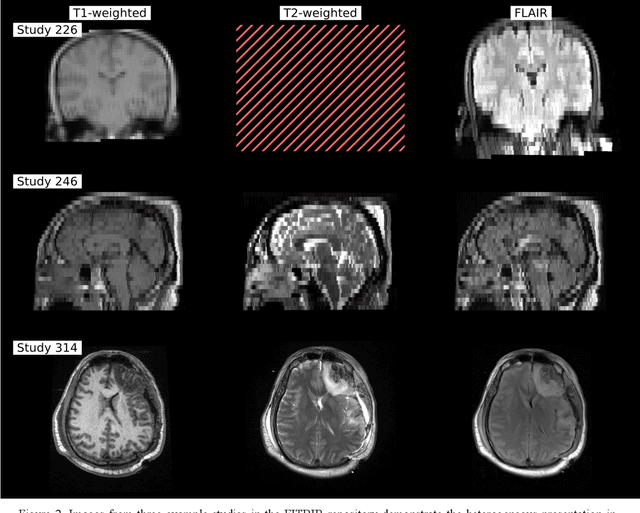

Abstract:Traumatic brain injury (TBI) is intrinsically heterogeneous, and typical clinical outcome measures like the Glasgow Coma Scale complicate this diversity. The large variability in severity and patient outcomes render it difficult to link structural damage to functional deficits. The Federal Interagency Traumatic Brain Injury Research (FITBIR) repository contains large-scale multi-site magnetic resonance imaging data of varying resolutions and acquisition parameters (25 shared studies with 7,693 sessions that have age, sex and TBI status defined - 5,811 TBI and 1,882 controls). To reveal shared pathways of injury of TBI through imaging, we analyzed T1-weighted images from these sessions by first harmonizing to a local dataset and segmenting 132 regions of interest (ROIs) in the brain. After running quality assurance, calculating the volumes of the ROIs, and removing outliers, we calculated the z-scores of volumes for all participants relative to the mean and standard deviation of the controls. We regressed out sex, age, and total brain volume with a multivariate linear regression, and we found significant differences in 37 ROIs between subjects with TBI and controls (p < 0.05 with independent t-tests with false discovery rate correction). We found that differences originated in 1) the brainstem, occipital pole and structures posterior to the orbit, 2) subcortical gray matter and insular cortex, and 3) cerebral and cerebellar white matter using independent component analysis and clustering the component loadings of those with TBI.